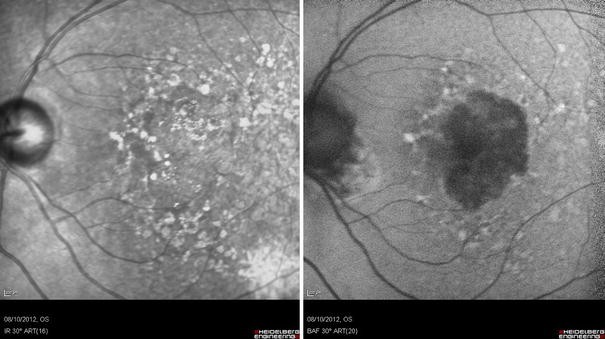

Near-infrared reflectance image (left) and blue light fundus autofluorescent image (right) demonstrating drusen and geographic atrophy in a patient with dry age-related macular degeneration (AMD)

In general, blue- and green-light FAF imaging has proven valuable for assessment of patients with AMD, in particular those patients with geographic atrophy [34, 40, 41]. In such patients, areas of atrophy appear hypoautofluorescent due to the confluent loss of RPE cells (and thus loss of the fluorescent signal generated from their lipofuscin granules). The boundaries of these atrophic areas are often more clearly visualized on FAF imaging than on conventional fundus photography (Fig. 2) [42]. A number of studies have also suggested that the autofluorescent patterns seen in the areas surrounding foci of geographic atrophy can be predictive of the rate of disease progression [40, 43].